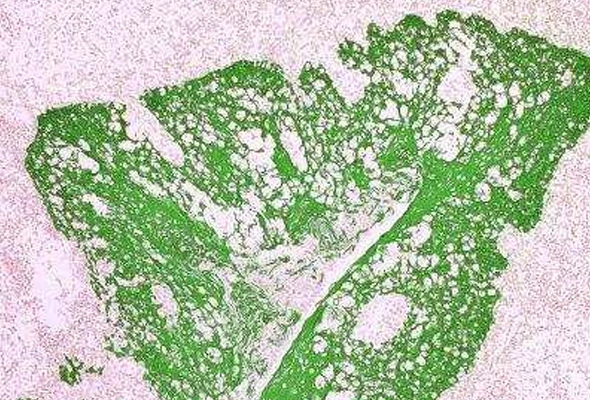

시약 및 기기 상세 [Novus] Tissue Glue Kit Maker : NOVUS BIOLOGICALS 조직절편을 유리 슬라이드에 단단하게 접착하기 위한 시약입니다. 프린트 제품 문의 특징 IHC 실험시, 조직 절편을 유리 슬라이드에 단단하게 접착하기 위해 이용됩니다. 특히 HIER (Heat-induced Epitope Retrieval) 과정시 고온을 이용하여 조직의 epitope를 복원할 때, 조직이 슬라이드에 강력히 부착되도록 유지시키는 데 유용합니다. 동결 조직 절편(frozen tissue sections) 및 파라핀 포매 조직 절편(paraffin-embedded tissue sections) 모두에 이용될 수 있습니다.최적의 결과를 위해서는 양전하를 띠는 유리 슬라이드를 사용하는 것이 좋습니다. Kit 구성품 Reagent 1 - 50 mL (조직과 슬라이드 모두에 부착 지점 형성)Reagent 2 - 50 mL (부착 지점들과 공유 결합함으로써 조직을 슬라이드에 영구적으로 단단하게 고정) 주문정보 견적문의 제품담기 주문정보 - Cat No, PRODUCT, SIZE, 수량 등 항목으로 구성되어있습니다. Product Cat.No. Size Maker Qty Data Sheet MSDS Tissue Glue Kit NBP3-12174 1 Kit NOVUS BIOLOGICALS - + 보기 보기 1 Maker NOVUS BIOLOGICALS Cat.No. NBP3-12174 Product Tissue Glue Kit Size 1 Kit Qty - + Data Sheet 보기 first 1 last 추천제품 [Novus] IHC Tissue Slides Immunohistochemistry 시약 (Coverslip Sealant, PAP Pen) AntiFix™ Universal Antigen Retrieval Buffer [Novus] Tissue Microarrays (TMA) [Novus] Primary Antibody | 1차 항체 관련제품 견적문의 제품담기 주문정보 - Cat No, PRODUCT, SIZE, 수량 등 항목으로 구성되어있습니다. Product Cat.No. Size Maker Qty Data Sheet MSDS 자료 웨비나/Video